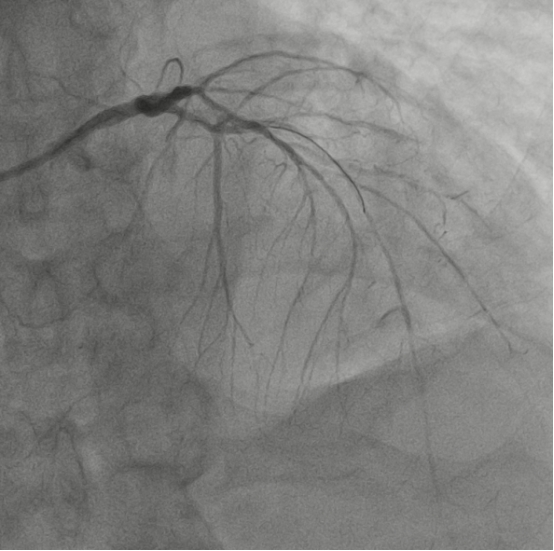

图3:右冠开通后

与死神的第一次交锋在介入室打响,胸痛中心介入团队在患者入院不到1小时便开通了右冠闭塞血管,患者胸痛症状明显缓解,术后送患者回CCU监护治疗,拟病情稳定后再处理左冠病变。